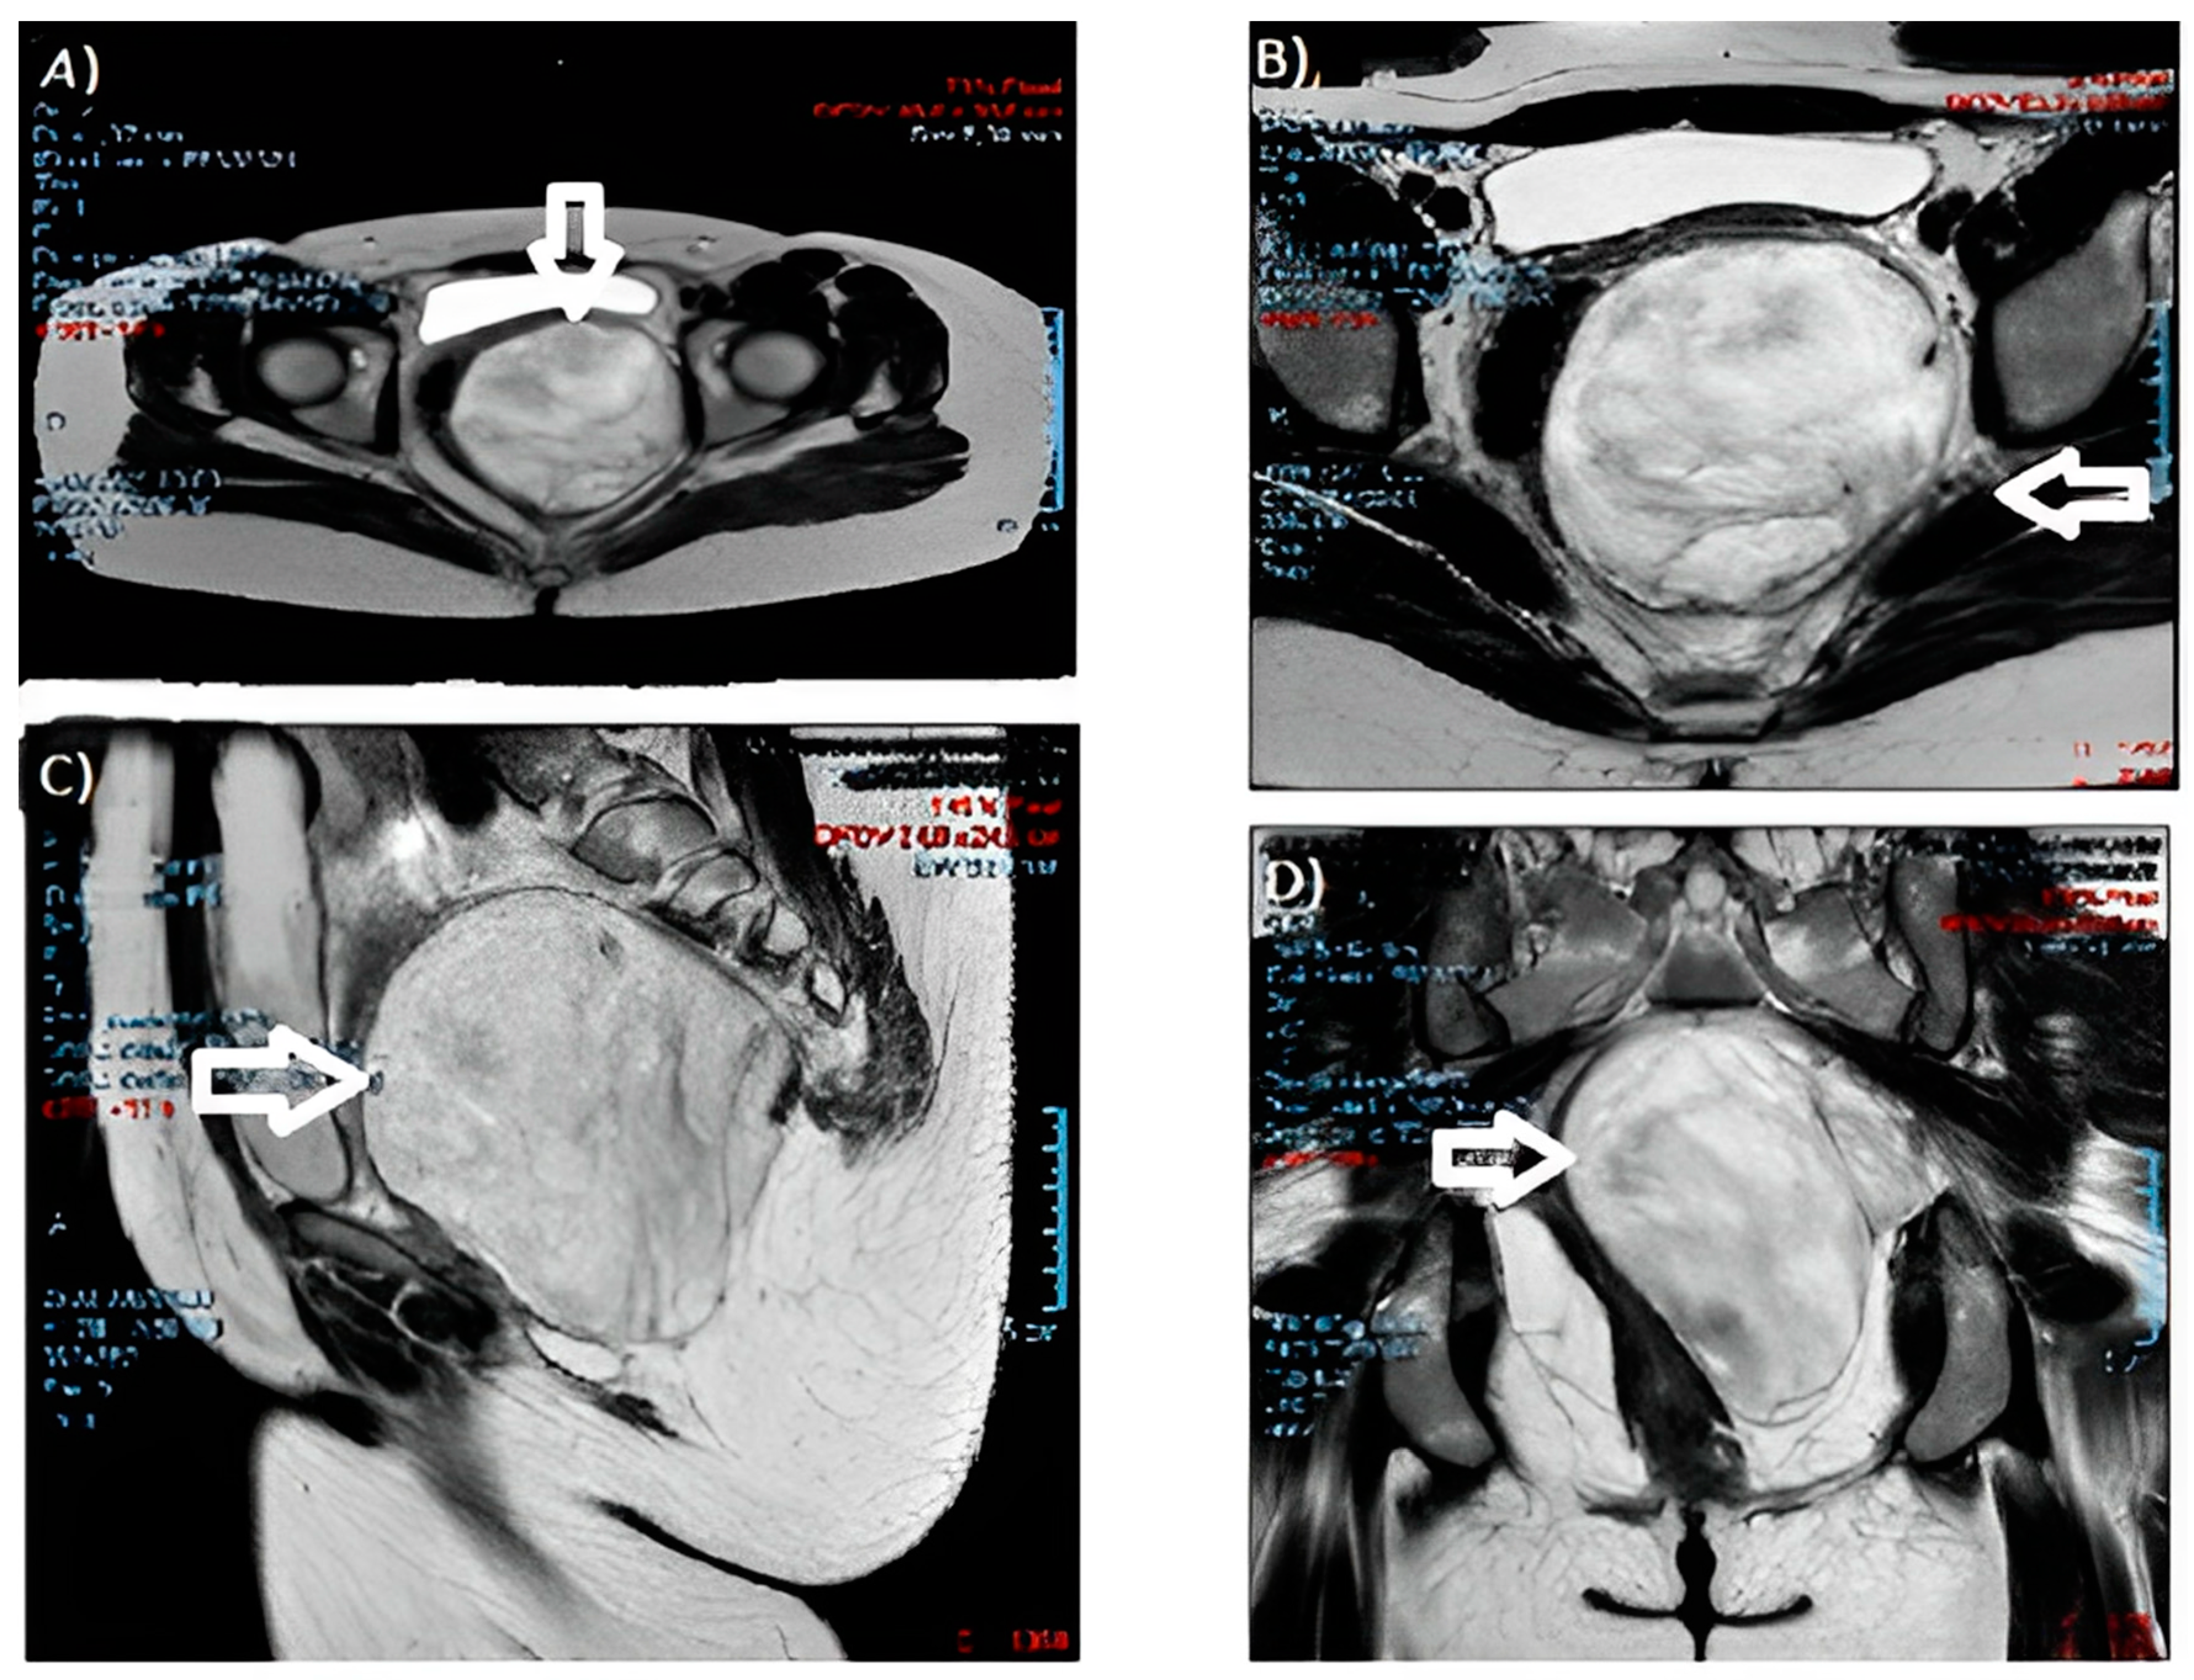

| 1 | Current case | 30 | Hypervascularized and inhomogeneous pelvic formation at ultrasound check | 10 cm in maximum diameter at 10 weeks of twin gestation | Left perineal area | Surgical excision at 13 weeks and 6 days; after, cesarean section at term |